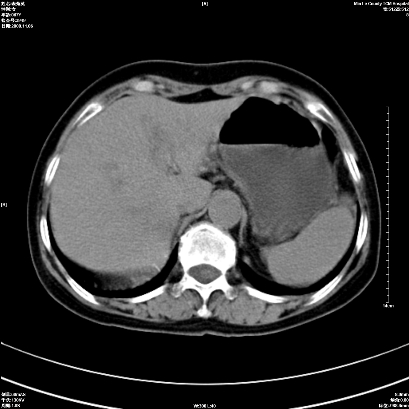

以下是引用卜一在2008-11-6 15:58:00的发言:[br]胰头略增大,胆总管扩张,末端渐行性狭窄。多考虑:胰头癌!建议增强!